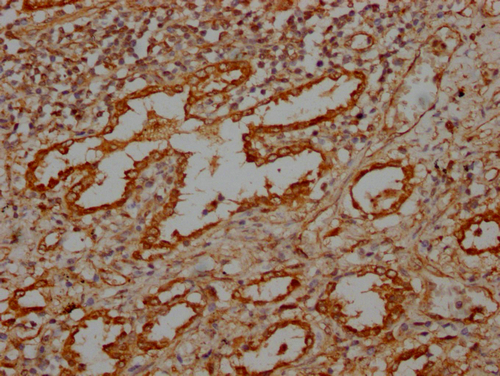

IHC image of CSB-PA617930LA01HU diluted at 1:100 and staining in paraffin-embedded human lung tissue performed on a Leica BondTM system. After dewaxing and hydration, antigen retrieval was mediated by high pressure in a citrate buffer (pH 6.0). Section was blocked with 10% normal goat serum 30min at RT. Then primary antibody (1% BSA) was incubated at 4°C overnight. The primary is detected by a Goat anti-rabbit IgG labeled by HRP and visualized using 0.05% DAB.